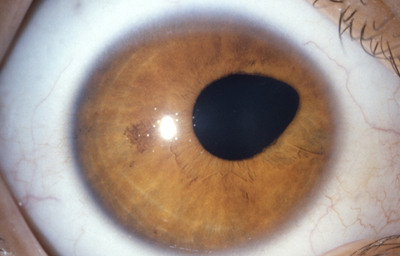

Desplazamientos y anormalidades en la forma de la pupila ( discória, corectópia y policória)

Los desplazamientos y malformaciones de la pupila forman un grupo aparte y diferente de los colobomas

Discória: Referente de las anomalías pupilares

Archivo Fotográfico Dr. Carmen Barraquer. 1989

Corectópia: la pupila en su totalidad, esta desplazada en cualquier dirección. En muchos casos el Iris es normal excepto por su dislocación respecto al centro de la córnea. En algunos casos, se logran ver finas bandas fibrosas que determinan el desplazamiento y se cree pueden ser fibras aberrantes zonulares ( vítreo terciario); otros, consideran que pueden venir de una etapa cuando el vítreo primario ya ha desaparecido, y el vítreo secundario ( condensado formando el Haz Istmico de Druault) todavía esta unido a mesodermo del Iris.

Es muy posible que la persistencia de cualquiera de esas bandas vítreas tempranas en continuidad con el mesodermo iridiano pueda producir una deformación pupilar; su naturaleza avascular y ectodérmica explicaría su aspecto clínico.

Policória: significa la presencia de varias pupilas en un Iris, es un hallazgo extremadamente raro, aclarando que el término se debe emplear solamente, para los casos en que la apertura esta rodeada por un esfínter completo; si no, es una policoria falsa.

Policoria falsa en midriasis OI: sinequia en el borde pupilar temporal con banda fibrosa 3 a 4; se ve el collarete y el esfínter periféricos a la pequeña pupila, lineas de tracción superiores e inferiores hacia el puente que separa las 2 aperturas de la 1 a las 5 - dentro de apertura pequeña, parece existir un remanente de membrana pupilar.

Archivo Fotográfico Dr. Carmen Barraquer. 1983